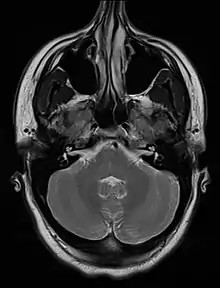

An MRI image showing a congenitally deviated nasal septum, bowed to the left between the eye sockets | |

The nasal septum is the bone and cartilage in the nose that separates the nasal cavity into the two nostrils. The cartilage is called the quadrangular cartilage and the bones comprising the septum include the maxillary crest, vomer, and the perpendicular plate of the ethmoid. Normally, the septum lies centrally, and thus the nasal passages are symmetrical.[2] A deviated septum is an abnormal condition in which the top of the cartilaginous ridge leans to the left or the right, causing obstruction of the affected nasal passage.